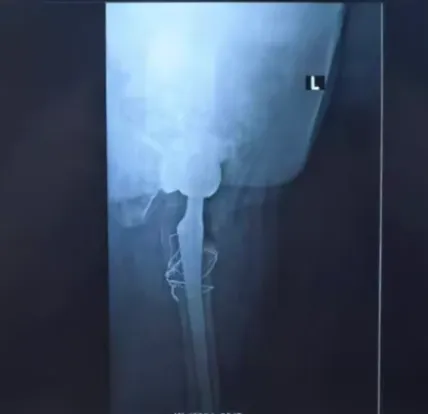

3. 股骨转子间骨折原则提倡复位固定,粗隆间骨折的患者做全髋关节置换手术难度徒升,此例患者因先髋,股骨头坏死多年,行全髋关节置换是唯一方案,更是三难合一难!因髋关节黏连,骨性强直,活动度差,术中钢丝捆绑骨折打入股骨柄也显得异常困难,而且极易导致骨折错位。

术后第二天,患者已下地负重行走,无不适主诉。从而免除长期卧床等待骨折愈合的痛苦,也避免了卧床相关并发症如坠积性肺炎、深静脉血栓,压疮等的发生。